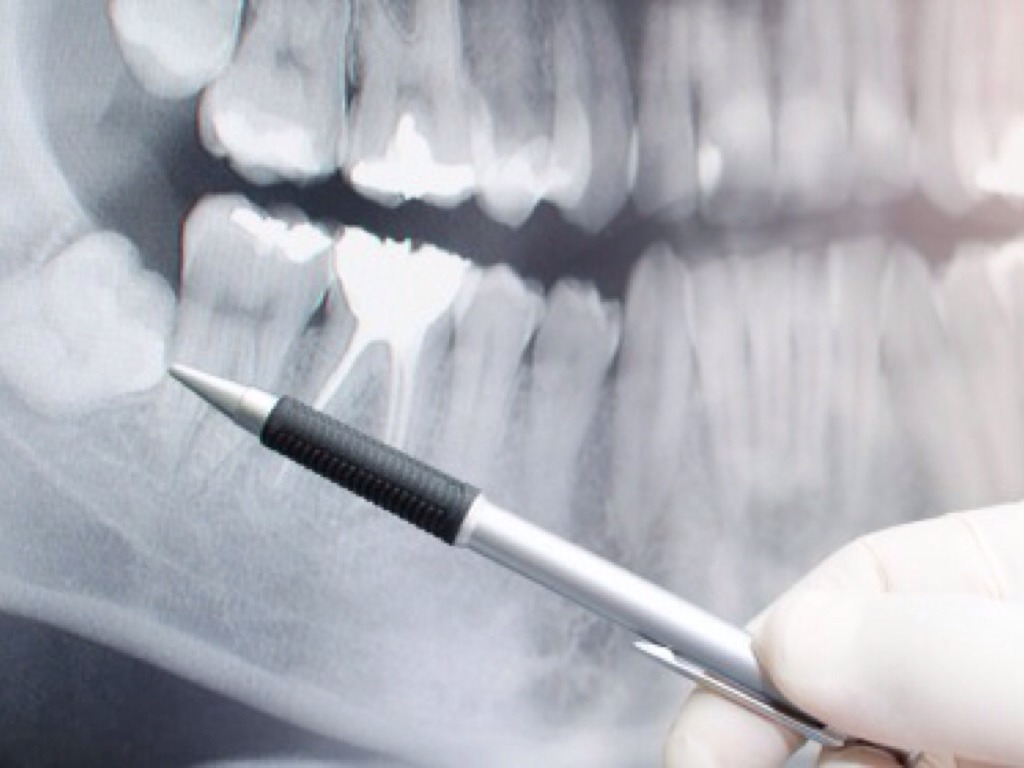

GROWTH PLATES